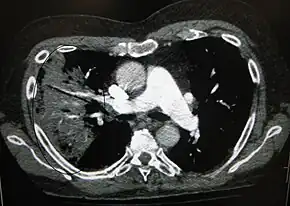

Cavitating pneumonia due to MRSA as seen on a CT scan

Bacteria are the most common cause of community-acquired pneumonia (CAP), with Streptococcus pneumoniae isolated in nearly 50% of cases.[34][35] Other commonly isolated bacteria include Haemophilus influenzae in 20%, Chlamydophila pneumoniae in 13%, and Mycoplasma pneumoniae in 3% of cases;[34] Staphylococcus aureus; Moraxella catarrhalis; and Legionella pneumophila.[18] A number of drug-resistant versions of the above infections are becoming more common, including drug-resistant Streptococcus pneumoniae (DRSP) and methicillin-resistant Staphylococcus aureus (MRSA).[21]